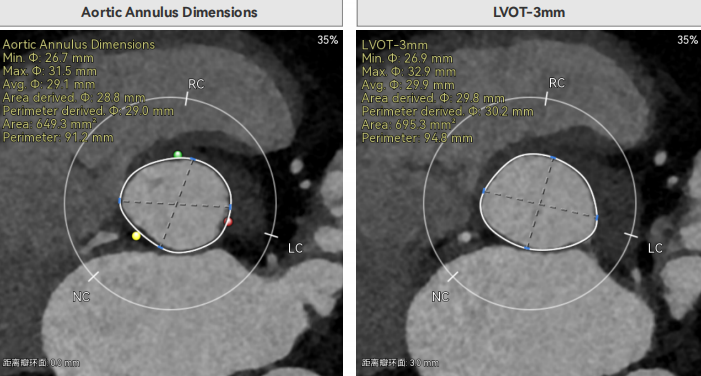

术前CT评估

Type1型二叶瓣(L-R),重度钙化、主要集中三窦瓣叶边缘及左右交界处,瓣上6-9mm区间;Annulus直径29mm,LVOT-5mm直径30.7mm,轻微扩张;瓣上12mm预估限制23.7mm,瓣上限制极重,封堵与锚定主要依赖瓣上限制;窦部空间正常、LR融合,瓣叶长度不超过冠脉开口上缘,无冠脉风险。左室腔扩大,有一定循环崩溃风险,主动脉瓣环水平夹角38.3°;外周股动脉弥漫钙化及粥样硬化性斑块、右股最窄直径5.4mm,左股条件较好,最窄直径6.0mm,双侧髂总动脉与主动脉弓底部存在较多钙化、通过有一定风险;右股低分叉。